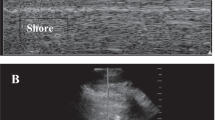

Normally, movement between visceral and parietal pleura results in a moving, shimmering pleural line known as lung sliding. Lung sliding at the parasternal areas rules out pneumothorax in the site of scanning with 100% negative predictive value [34, 35]. M-mode can be used to confirm a dynamic pleural line through distal artifacts in a granular pattern resembling sand on a beach, sometimes referred to as the “seashore sign”. In addition, hyperechoic, horizontal lines known as A-lines can be seen at regular intervals from the pleural line and represent reverberation artifacts in the air-filled lung. Together, A-lines and lung sliding represent an intact pleural line with normal content of air in the alveolar spaces (Fig. 2a).

Pneumothorax

A static pleural line suggests the absence of lung sliding, and in M-mode this is represented by a barcode appearance (Fig. 2b). Although the absence of lung sliding suggests possible pneumothorax, it is important to note that the lack of lung sliding and horizontal pleural movement can also be caused by adhesions, very low lung compliance, massive atelectasis, or in an apneic patient or main-stem intubation. Other signs like the lung pulse and B-lines, both described in more detail below, are artifacts which can only exist in the present of an intact visceral and parietal pleural, and thus their presence—even in the absence of lung sliding—rules out a pneumothorax at the scanned site [33, 34].

When this pattern suggests a pneumothorax (no lung sliding, lung pulse, or B-lines), the most definitive way to confirm the pneumothorax is to identify the lung point, or the dynamic transition point between normal, sliding lung and the absence of lung sliding. It is highly specific (98–100%) for diagnosing a pneumothorax [35, 36]. To find the lung point, the probe is gradually moved towards the lateral-inferior chest areas to find a point on the chest wall where there is re-visualization of a respiratory pattern (e.g., lung sliding) that is intermittently replaced by motionless pleura, corresponding to the edge of the intrapleural air layer. In M-mode, the lung point appears as an abrupt transition from a barcode appearance to the “seashore sign” (Fig. 2b).